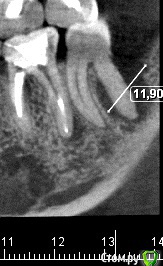

ceti Опубликовано 21 декабря, 2015 Автор Поделиться Опубликовано 21 декабря, 2015 Здравствуйте! По результатам очного осмотра доктор исключил трещину и предположил парадонтальную проблему. Есть какое-то объяснение, что могло послужить причиной и почему процесс так быстро прогрессировал? Ниже фрагмент КТ, который был сделан в феврале этого года и свежий снимок: Заранее благодарю. Ссылка на комментарий